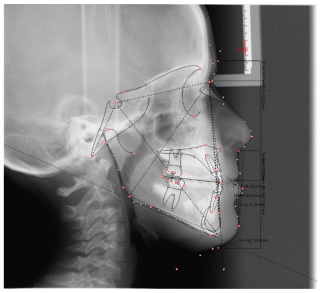

Case 2

The patient was a growing female child who presented during early mixed dentition with an anterior crossbite associated with a deep overbite and a marked sagittal discrepancy (Figures 12–19). The initial clinical examination revealed a negative overjet, complete anterior deep bite, and a functional Class III occlusal pattern. Extraoral assessment showed a flattened facial profile, while cephalometric analysis confirmed a skeletal imbalance characterized by increased SNA and SNB values, an ANB of 0°, negative Withs appraisal, and significant dentoalveolar compensations, including proclination of both upper and lower incisors (Table 3). The vertical pattern was predominantly hypodivergent, suggesting a high risk of unfavorable mandibular growth progression if left untreated. Given the patient’s young age and growth potential, an early interceptive treatment was planned to use the AMCOP® TC appliance, with the aim of correcting the anterior crossbite, improving neuromuscular balance, and guiding sagittal and vertical development during growth. The appliance was worn nightly and for additional daytime hours, according to patient compliance.

After 18 months of treatment, a clear clinical improvement was observed. Intraoral examination demonstrated complete correction of the anterior crossbite, with establishment of a positive overjet and normalization of the anterior occlusal relationship. The deep bite was reduced, allowing more functional anterior guidance. Occlusal relationships improved toward a stable dental Class I, and the need for excessive dentoalveolar compensation was reduced. Cephalometric reassessment showed an overall improvement in sagittal relationships and incisor inclinations, with a trend toward normalization of the previously altered parameters. These findings indicate that early functional therapy with the AMCOP® TC appliance was effective in intercepting the developing Class III malocclusion, improving occlusal function, and potentially reducing the severity of future skeletal discrepancies (Table 4).